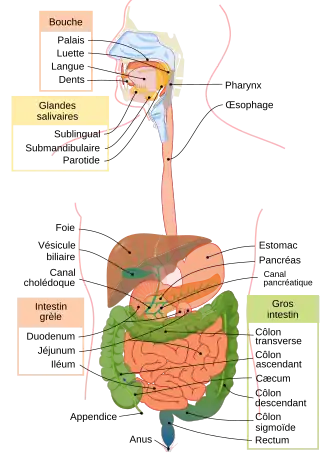

Le foie est le plus gros organe abdominal et fait partie de l'appareil digestif sécrétant la bile et remplissant plus de 300 fonctions vitales[1], notamment les trois suivantes : une fonction d'épuration, une fonction de synthèse et une fonction de stockage. Il s'agit d'une glande amphicrine permettant la synthèse de la bile (rôle exocrine) ainsi que celle de plusieurs glucides et lipides (rôle endocrine). Il joue aussi un rôle important dans l'hémostase. Il s'agit d'un organe richement vascularisé.

Le foie humain

Chez l'humain, il est impair et asymétrique. Il est logé dans l'hypocondre droit, la loge sous-phrénique droite, la partie supérieure du creux épigastrique puis atteint l'hypochondre gauche. C'est le plus volumineux des viscères abdominaux (2 % du poids corporel, soit une moyenne de 1 500 grammes pour une vingtaine de centimètres de long[1]) et l'organe du corps humain qui effectue le plus grand nombre de transformations chimiques. La discipline médicale qui lui est rattachée se nomme l'hépatologie. Le foie contient près de 13 % de la quantité de sang présent dans notre corps. Il peut connaitre des variations de volume allant jusqu'à 40 %[1].

Anatomie

Le foie est un organe intrapéritonéal : il est recouvert à sa surface de péritoine viscéral, qui le rattache à la paroi abdominale en se réfléchissant sur le péritoine pariétal. La capsule de péritoine viscérale qui l'entoure est appelée la capsule de Läennec. Toutefois, elle possède une zone non péritonisée appelée l'area nuda, située en arrière et contre le diaphragme. De plus, le foie est entièrement recouvert d'une capsule fibreuse sous-jacente au péritoine viscéral, appelée la capsule de Glisson.

On distingue habituellement deux faces au foie :

- une face diaphragmatique, lisse et en forme de dôme qui épouse la concavité du diaphragme ;

- une face viscérale, plane et présentant de nombreux replis de péritoine et des fissures.

La face diaphragmatique est séparée de la face viscérale en avant par le bord inférieur, qui est aigu et dit « tranchant », en regard du rebord costal inférieur, et en arrière par le bord postérieur, qui est plus arrondi.

Le ligament falciforme, issu du mésentère ventral lors du développement embryonnaire, relie le foie à la paroi abdominale antérieure. C'est un repli de péritoine tendu verticalement depuis l'appendice xiphoïde et le diaphragme jusqu'à l'ombilic. Il contient entre ses deux feuillets le ligament rond du foie, vestige de la veine ombilicale qui s'oblitère après la naissance. Ce ligament falciforme est continu avec la capsule de Glisson qui entoure le foie : sur la face antéro-supérieure (face diaphragmatique), il sépare le foie en deux parties gauche et droite, souvent considérées comme des lobes droit et gauche du foie. Sur la face viscérale, le ligament falciforme se continue par la capsule, tandis que le ligament rond qu'il contient s'insère dans la moitié antérieure d'un sillon appelé le sillon sagittal gauche.

On distingue donc au foie deux lobes — gauche et droit — sur la face diaphragmatique du foie, marqué par l'insertion du ligament falciforme. Cette subdivision du foie repose uniquement sur un critère anatomique : on ne devrait pas parler de « lobe », car la lobulation d'une glande repose sur d'autres critères structuraux, notamment la présence de septa conjonctifs qui viennent séparer la glande en plusieurs unités fonctionnelles. Le lobe droit du foie est le plus volumineux, tandis que le lobe gauche est petit et se termine en pointe (apex du foie).

En plus de ces deux lobes principaux, on distingue deux petits lobes à la face viscérale du foie : le lobe caudé et le lobe carré.

Face viscérale

La face viscérale du foie occupe la partie inférieure du foie, dans le plan transversal, et regard en arrière, en bas et à gauche. Elle présente deux fissures sagittales et une fissure transversale qui lie ces dernières et forme un « H » :

- la fissure sagittale droite (ou sillon sagittal droit) correspond à la fosse de la vésicule biliaire en avant, et au sillon de la veine cave inférieur en arrière ;

- la fissure sagittale gauche (ou sillon sagittal gauche) est le sillon continu formé par la fissure du ligament rond en avant, et par la fissure du ligament veineux en arrière. Le ligament rond du foie est le reliquat fibreux de la veine ombilicale, qui transporte le sang bien oxygéné et riche en nutriments, du placenta au fœtus. Le ligament veineux est également un vestige, du conduit veineux, qui court-circuite la circulation hépatique et achemine ainsi les nutriments du placenta à la circulation systémique. Lors de la naissance, ces deux veines s’oblitèrent en tissu fibreux (ligaments) ;

- le sillon transversal relie en arrière les deux sillons sagittaux et forme le hile du foie (ou porte du foie), point de passage des vaisseaux vasculaires et lymphatiques, des nerfs et des conduits biliaires.

C'est donc par la face viscérale que rentrent et sortent des structures telles que des vaisseaux sanguins et lymphatiques, nerfs et conduits biliaires, au niveau de la porte du foie (hile hépatique) : la porte du foie sert de porte de rentrée pour l'artère hépatique propre, la veine porte hépatique et les lymphonoeuds hépatiques, et de point de sortie pour les conduits biliaires (conduit hépatique commun et cystique, formant le cholédoque à la sortie du hile).

La face viscérale présente deux petits lobes accessoires : le lobe carré et le lobe caudé.

Vascularisation

Les vaisseaux qui irriguent et drainent le foie sont regroupés en trois groupes[7] :

- les vaisseaux du pédicule hépatique (vaisseaux afférents), comprennent les artères hépatiques propres qui va donner l’artère hépatique droite et gauche, le système porte et le tronc hépatique provenant l’artère coronaire stomachique. Ils acheminent le sang artériel et veineux vers les sinusoïdes hépatiques ;

- les veines hépatiques (ou sus-hépatiques), qui drainent le sang et le ramènent dans le circuit systémique en s'abouchant dans la veine cave inférieure ;

- les vaisseaux accessoires, qui ont une origine variée et inconstante.

L'apport sanguin est réalisé par l'artère hépatique propre, amenant le sang oxygéné, et par la veine porte ramenant le sang du tube digestif, du pancréas et de la rate riche en nutriments en période postprandiale. Le sang de ces deux vaisseaux se mélange dans les sinusoïdes hépatiques qui cheminent entre les travées hépatocytes pour se réunir dans une veine centrolobulaire. En période post-prandiale, environ 70 % du sang est issu de la veine porte hépatique, et 30 % de l'artère hépatique propre. Le sang veineux porte est riche en nutriments, tandis que le sang artériel sert principalement à l'apport d'oxygène. La vascularisation hépatique est dite mixte. Le foie contient près de 13 % de la quantité de sang présent dans notre corps, avec une augmentation importante du volume la nuit, jusqu'à 40 %[1].

L'artère hépatique propre est la branche terminale de l'artère hépatique commune, issue du tronc cœliaque. L'artère hépatique commune donne sur son chemin les artères gastrique droite et gastroduodénale avant de devenir l'artère hépatique propre, qui remonte vers le hile hépatique (porte du foie). Une fois dans la porte du foie, l'artère hépatique propre bifurque en deux branches principales, les branches hépatiques droite et gauche, de la même manière que la veine porte hépatique se divise en deux branches droite et gauche.

Du fait de cette bifurcation des vaisseaux afférents, ainsi que des conduits biliaires, on divise arbitrairement le foie en deux compartiments lobaires : le foie droit et le foie gauche. Cette compartimentation repose sur des critères structurels et fonctionnels qui sont interne au foie. Sur le plan anatomique de surface, on divise habituellement le foie en deux lobes par l'insertion du ligament falciforme : les deux lobes « anatomiques » ne sont pas les mêmes que ceux qui viennent d'être cités. De plus, on peut considérer le lobe caudé du foie comme un troisième lobe fonctionnel, car il reçoit des artères et des veines des deux branches principales (veines et artères) caudées droite et gauche.

Le retour veineux du foie s'effectue par les veines hépatiques, également appelées veines sus-hépatiques, qui se jettent dans la veine cave inférieure. On distingue trois veines hépatiques : la veine hépatique droite, moyenne, et gauche.

Lobes du foie

Le foie est divisé en deux lobes séparés par le ligament falciforme (ou ligament suspenseur)[8], le lobe droit (deux tiers du volume du foie) et le lobe gauche (un tiers du volume). On peut également individualiser deux autres lobes mineurs en taille : le lobe caudé (ou lobe de Spiegel) et le lobe carré[9].

Le lobe caudé, également appelé lobe de Spiegel, est visible à la partie postérieure de la face viscérale du foie, et est limité sur sa gauche par le sillon du ligament veineux (sillon sagittal gauche), sur sa droite par le sillon de la veine cave inférieure (sillon sagittal droit) et finalement en avant par le hile du foie. Il est nommé ainsi car il est muni d'un prolongement allongé en forme de queue, le processus caudé, qui rejoint le processus papillaire (faisant également partie du lobe caudé). Sur le plan anatomique comme fonctionnel, il est considéré comme un lobe individuel : sur le plan anatomique, grâce aux limites citées précédemment, et sur le plan fonctionnel, par l'apport vasculaire. Il est vascularisé par des vaisseaux afférents venant des foies droit et gauche (veines et artères caudées gauches et droites).

Le lobe carré du foie est visible est à la partie antérieure de la face viscérale du foie. Il est limite sur la gauche par le sillon du ligament rond (partie antérieure du sillon sagittale gauche), à droite par le fond de la vésicule biliaire (fundus) et en arrière par le hile du foie.

Cette subdivision du foie en plusieurs lobes — deux lobes principaux et deux lobes accessoires — repose sur des critères anatomiques et ne correspondent pas aux critères de lobes d'une glande. Cette subdivision est donc purement obsolète, et les lobes anatomiques ne sont pas séparés par des septa conjonctifs entre deux.

Segmentation hépatique

La segmentation hépatique est une division du foie en plusieurs segments, adaptée particulièrement pour la résection chirurgicale. Elle repose essentiellement sur une division fonctionnelle du foie : le foie est ainsi divisé en territoires fonctionnels dénommés secteurs et segments. Elle relève de nombreux travaux, notamment ceux de Cantlie (1898), Hjörstjö (1931), Harley et Schroy (1953), Goldsmith et Woodburne (1957) et Couinaud (1957).

Selon la segmentation hépatique de Couinaud[10], le foie est divisé en secteurs, eux-mêmes divisés en segments.

Les veines sus-hépatiques délimitent le foie en secteurs : la veine sus-hépatique gauche sépare le secteur latéral gauche du secteur paramédian gauche, la veine sus-hépatique médiane sépare le foie droit du foie gauche c'est-à-dire le secteur paramédian gauche du secteur antérieur droit (ou secteur paramédian droit) et la veine sus-hépatique droite sépare le secteur antérieur droit du secteur postérieur droit (ou secteur latéral droit)[8].

Les branches de division de la veine porte délimitent les secteurs du foie en huit segments numérotés de I à VIII sur la face inférieure du foie dans le sens inverse des aiguilles d'une montre[11] :

- le segment I correspond au lobe caudé et à la partie du foie en avant de la veine cave ;

- les segments II et III correspondent au secteur latéral gauche ;

- le segment IV correspond au secteur médial gauche ;

- le segment V correspond à la partie inférieure et le segment VIII à la partie supérieure du segment antérieur droit ;

- le segment VI correspond à la partie inférieure et le segment VII à la partie supérieure du segment postérieur droit.

En chirurgie, on décompose ainsi le foie en deux hémi-foies qui correspondent aux ramifications vasculaires. Ainsi, le « foie » gauche reçoit la branche gauche de division de l'artère hépatique et de la veine porte, le « foie » droit la branche droite de ces vaisseaux. Le foie gauche comporte les segments II, III et IV ; le foie droit comporte les segments V, VI, VII et VIII. Le segment I est quant à lui partagé entre les deux. Cette segmentation est essentielle pour la chirurgie hépatique puisqu'elle permet l'ablation d'un segment sans gêner la vascularisation des autres segments.

Cette division fonctionnelle ne se recoupe pas complètement avec la division anatomique[9] :

- le lobe droit comprend le foie droit plus le segment IV, soit les segments IV, V, VI, VII et VIII ;

- le lobe gauche comprend le foie gauche moins le segment IV, soit les segments II et III ;

- le lobe caudé correspond au segment I ;

- le lobe carré correspond à la base du segment IV.

Voies biliaires intra- et extrahépatiques

Les hépatocytes sécrètent la bile dans les canalicules biliaires. Ceux-ci sont formés par des invaginations de la membrane plasmique des hépatocytes et forment en fait un espace virtuel. Les canalicules de chaque hépatocyte se déversent dans un canal biliaire primitif appelé canal de Hering. Par la suite, la bile poursuit son parcours dans des canaux biliaires interlobulaires lesquels sont constitués de cellules biliaires (cholangiocytes) qui reposent sur une lame basale. Les canaux interlobulaires forment ensuite des canaux biliaires de plus gros calibre et finissent par former les canaux hépatiques droit et gauche dont la réunion forme le canal hépatique commun qui quitte le foie au niveau du hile hépatique. Le canal cystique issu de la vésicule biliaire se jette dans le canal hépatique commun qui devient le cholédoque, lequel s'abouche dans le duodénum.